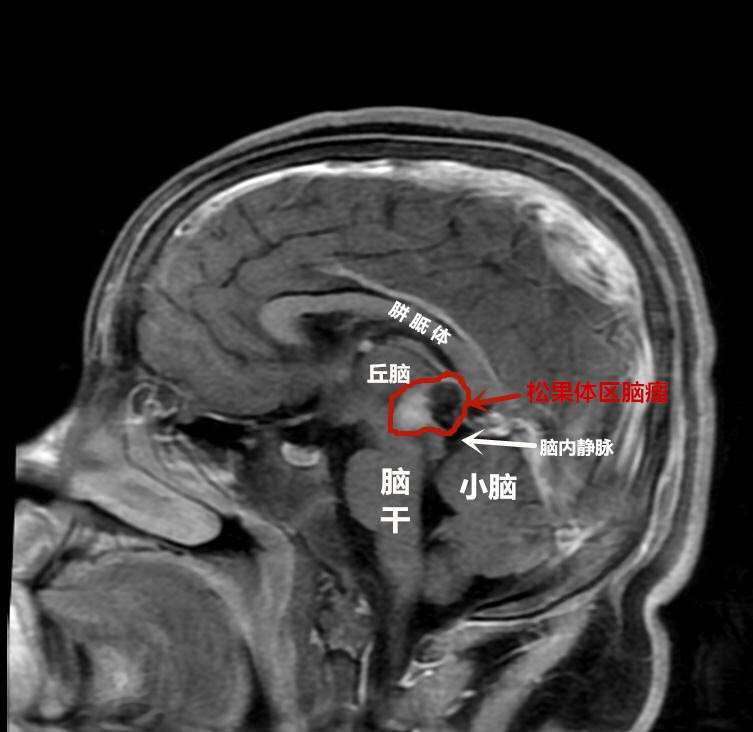

6月初,学校老师曾向军军的父母反映孩子上课总趴在课桌上,显得没精神,起先还没引起重视,随后军军开始频繁起夜,总是凌晨三四点喊头疼,然后到厕所里呕吐,父母着急了,带他到附近医院,当成鼻炎、胃病吃药治疗,折腾了近半个月也不见好。眼见原来的小胖墩消瘦了近10斤,一家人十分着急,到当地某大医院检查,才吃惊地发现,孩子的一切病症均因大脑中央的脑瘤导致,已出现了急性重度脑积水。

术前

为求进一步治疗,当天夜里他们便辗转到武汉脑科医院·长江航运总医院小儿神经外科。此时,军军随时都有生命危险,该科专家邵强主任连夜组织急诊手术。好在通过抢救及时保住了孩子的生命,一周后随着颅内压降低,邵强团队为军军进行了开颅手术,进行了分块全切脑瘤。邵强称,虽然患儿的肿瘤体积不大,但稍有不慎就会损伤正常脑组织和血管,引发昏迷,甚至大出血,可谓危险重重。